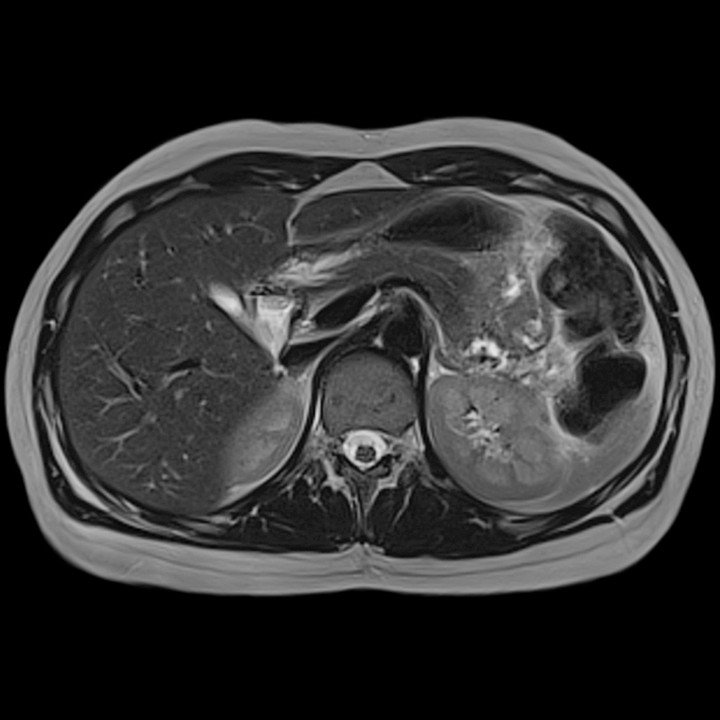

Written by Judy Gichoya and Alexandre Cadrin-Chênevert recenty directed a post to us from one of the fast.ai student asking about housefield units conversion for MRI. Jeremy Howard Question This post summarizes an overview of the physics of image formation for MRI and CT scans to help understand the concept of intensities and mapping For the impatient reader, answered this question Alexandre Cadrin-Chênevert If this of interest then read on…. What is a modality ? Radiology relies on various types of cameras (or ) — that work differently to capture images from patients. These include ultrasound , Computed Tomography (CT scan), Magnetic Resonance Imaging (MRI), PET/CT , and plain Xray. Yes, think of the various modalities related to the different camera types for medical imaging. In the picture below, you can see the appearance of the liver across different cameras (modalities) modalities Liver images aquired through ultrasound Images of the liver / upper abdomen acquired from an MRI CT scan images of the upper abdomen including liver How are MRI images formed? MRI physics can be summarized as . signal generation , image formation and sequences A: Signal Generation Our bodies are made largely of water (72% of our bodies are made up of water). Water is composed of 2 Hydrogen molecules and 1 oxygen molecule (H20). This translates to a large amount of hydrogen molecules in our bodies. Hydrogen is a chemical element with an atomic number 1 (H+). Water composition in the human body The MRI machine is a big strong magnet (and the unit Tesla is used to signify the strength of the main magnet). When you are sitting at the core of the MRI machine for example for a Head MRI , then most of the hydrogen atoms in your body align to the direction of the main magnet (b0). This is called longitudinal magnetizaton. At rest, all your hydrogen atoms are spinning on their axis — Watch the video tagged below to learn about precession Since we know the main magnet strength (B0), then we can calculate Lamor frequency which can be used to generate signal to the hydrogen atoms that in precession. lamor frequency In the figure above, the H+ are at a precession frequency of 64 MHz evenly distributed across the magnetic field. The knowledge of the precession frequencies allows us to focus on a section of the body eg abdomen by shifting the magnetic field so we can apply a signal to a specific group of atoms rotating at a predetermined frequency. In addition to the main magnetic field, the MR machine has a radiofrequency (RF) signal that is applied perpedicular (90 degrees) to the main magnet and flips the hydrogen atoms to 90 degrees relative to the main magnet. I like to think of this as the process of tuning in to the radio where you are always looking for a specific frequency. This is called . The hydrogen atoms continue their precession, but also lose energy to go to a lower energy state (in the direction of the main magnet). transverse magnetization The above steps are summarized below …. Recap of signal generation As the hydrogen atoms lose energy to align themseves to the direction of the main magnet ( ), the signal they generate can be captured and plotted as a curve shown below. This curve is used to determine the — longitudinal relaxation T1 time T — T1 time which is the time require for protons to recover 63% of their longitudinal magnetization. T1 — time required for protons to recover 63% of their longitudinal magnetization Different body tissues will have different T1 times , and hence when you look at an MRI , you can identify fat (short T1) versus CSF. Difference in T1 curves across various tissues Another phenomenon that is occuring after the 90 degrees RF is summarized below. The hydrogen atoms are in phase at the beginning of the 90 degree RF pulse, but they undergo a spin -lattice interaction and get out of phase. If you plot this curve of , then you get a free induction decay T2* curve. T2 * curve T T2 time — is the time required for protons to lose 63% of their transverse magnetization. Now that we have explained T1 and T2 signals, we will move on to an example of meningioma to help understand the MR signals. Please note physics MR is a wide topic and we have not described concepts like diffusion , echo, gradient and TOF sequences,as well as artifacts . works by shifting the T1 curve to the left (shortens the T1 curve). Contrast Meningioma on MR In the above image, the left image is and the meningioma is difficult to identify. After administration of IV contrast (gadolinium), the T1 curve of meningioma shifts to the left and is seen as an enhancing lesion on the right image. T1 weighted image, CT physics — Hounsfield units (HU) CT images are not developed based on the hydrogen magic for MR. Instead , they use Xrays, a form of radiation focussed on part of the body being imaged. Different parts of the body (weaken) the Xray beam at different rates. Therefore to standardize the different values of attenuation, the is used to measure how easily a beam penetrates a a material. Since we know the attenuation of water to be zero, then the HU is calculated relative to water. attenuate attenuation coefficient HU calculation Therefore by measuring a region of interest, you can calculate the HU of a lesion and determine what it is — for example a fat containing lesion or a fluid containing lesion as a cyst. http://www.odec.ca/projects/2007/kimj7j2/index_files/Page1674.htm Tying it together (Deep Learning) Image segmentation is the process of drawing contours of an object to delineate its boundaries. In medical imaging, segmentation allows surface or volumetric quantification of a lesion or an anatomic structure. To train this kind of model, you need to show multiple images iteratively to the model with the associated segmented areas, often drawn manually by radiologists. U-Net is a specialized deep learning model architecture that allows automatic segmentation. U-Net: Convolutional Networks for Biomedical Image Segmentation From : U-Net: Convolutional Networks for Biomedical Image Segmentation ( ) https://arxiv.org/pdf/1505.04597.pdf U-net is designed intrinsically to perform very well with a small number of training cases. The architecture progressively encodes the initial image in a numerically squeezed representation, literally at the bottom of the U. Then, this bottom representation is decoded symmetrically to generate the automatic segmented area, also defined as a mask, as the final output. The training is optimized to minimize the difference between the proposed segmented area with the manually segmented ground-truth area. This property that allows an efficient training with a very small number of cases is particularly useful in medical imaging where expert manual segmentation is very costly. For meningioma segmentation, this technique could intuitively be tried on a post-gadolinium MRI sequence which is the sequence with the according to this pathology (i.e. meningiomas typically show avid enhancement, and bright signal, relative to the background). highest signal to noise ratio Hopefully this clarifies the idea of signals across CT and MR and helps you on your deep learning path. Consider joining our community that intersects radiology and imaging sciences with deep learning scientists here : . https://tribe.radai.club We discuss deep learning on our monthly journal club archived here : . Our next journal club is on 22nd February , 8 pm EST with a presentation from on — https://youtu.be/xoUpKjxbeC0 Timnit Gebru “Using deep learning and Google Street View to estimate the demographic makeup of neighborhoods across the United States” https://register.gotowebinar.com/register/8696551324404512003 Say thanks and references Numerous images of physics lecture were obtained from one of my best teachers at — Indiana University Radiology Department Dr. Isaac Wu Read more about MR physics here — MRI made easy